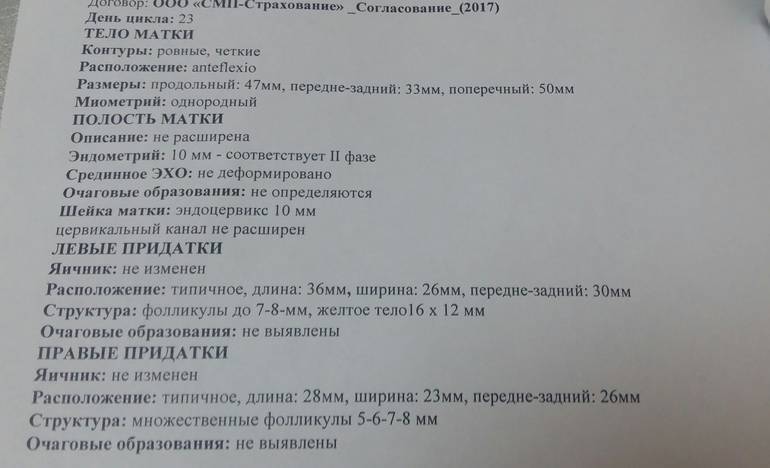

Созревание фолликула в яичнике: этапы и процессы